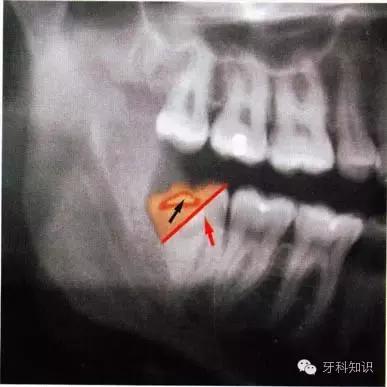

术前观察阻生牙远中牙槽嵴的情况。图a中,可直接拔除;图b中,则需去除远中骨壁或分根

全颌曲面断层×线片。切割牙冠时应经过阻生牙远中面的牙颈部的釉牙骨质交界处

下颌升支前缘的骨吸收区有利于牙片的取出